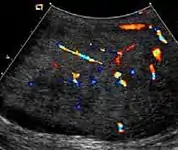

Epididymo-orchitis in a 77-year-old man. (a) Transverse sonography shows enlargement of the epididymis with hypoechogenicity noted over the testis and epididymis associated with scrotal wall thickening. (b) Color Doppler sonography showed hyperemic change of the testis and epididymis, presenting as an “inferno” vascular flow pattern.

Epididymitis and epididymo-orchitis are common causes of acute scrotal pain in adolescent boys and adults. At physical examination, they usually are palpable as tender and enlarged structures. Clinically, this disease can be differentiated from torsion of the spermatic cord by elevation of the testes above the pubic symphysis. If scrotal pain decreases, it is more likely to be due to epidiymitis rather than torsion (Prehn's sign). Most cases of epididymitis are secondary to sexually transmitted disease or retrograde bacteria infection from the urinary bladder.[4] The infection usually begins in the epididymal tail and spreads to the epididymal body and head. Approximately 20% to 40% of cases are associated with orchitis due to direct spread of infection into the testis.

At ultrasound, the findings of acute epididymitis include an enlarged hypoechoic or hyperechoic (presumably secondary to hemorrhage) epididymis [Fig. 20a]. Other signs of inflammation such as increased vascularity, reactive hydrocele, pyocele and scrotal wall thickening may also be present. Testicular involvement is confirmed by the presence of testicular enlargement and an inhomogeneous echotexture. Hypervascularity on color Doppler images [Fig. 20b] is a well-established diagnostic criterion and may be the only imaging finding of epididymo-orchitis in some men.